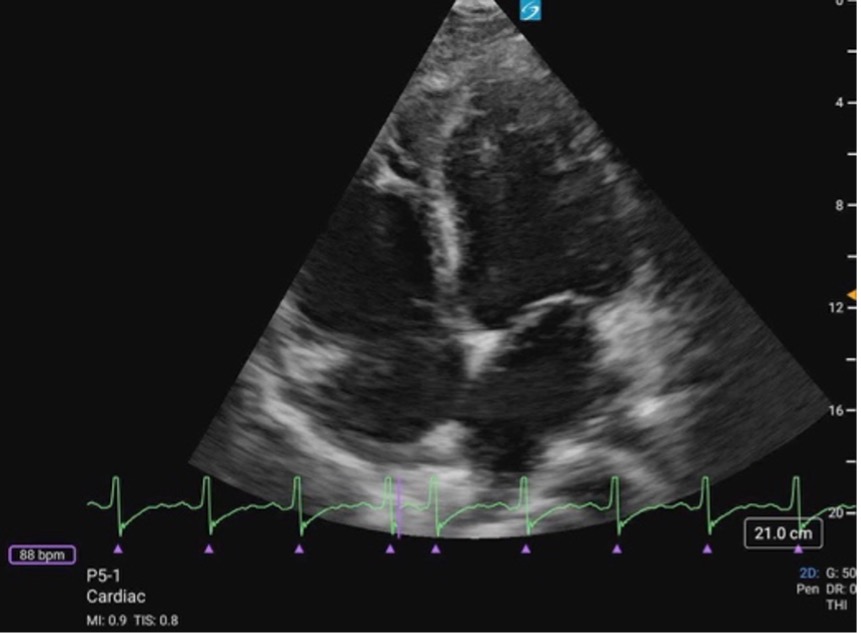

Subcostal Four Chamber

What am I Looking at?

The subxiphoid 4 Chamber view can be used to assess ventricular function, particularly during emergent situations, when access to the other windows is limited.

The left ventricle is seen in the far field with the septal and lateral walls in view. The RV is seen more anteriorly.

Figure 25. Subxiphoid 4 chamber with the LV walls labeled